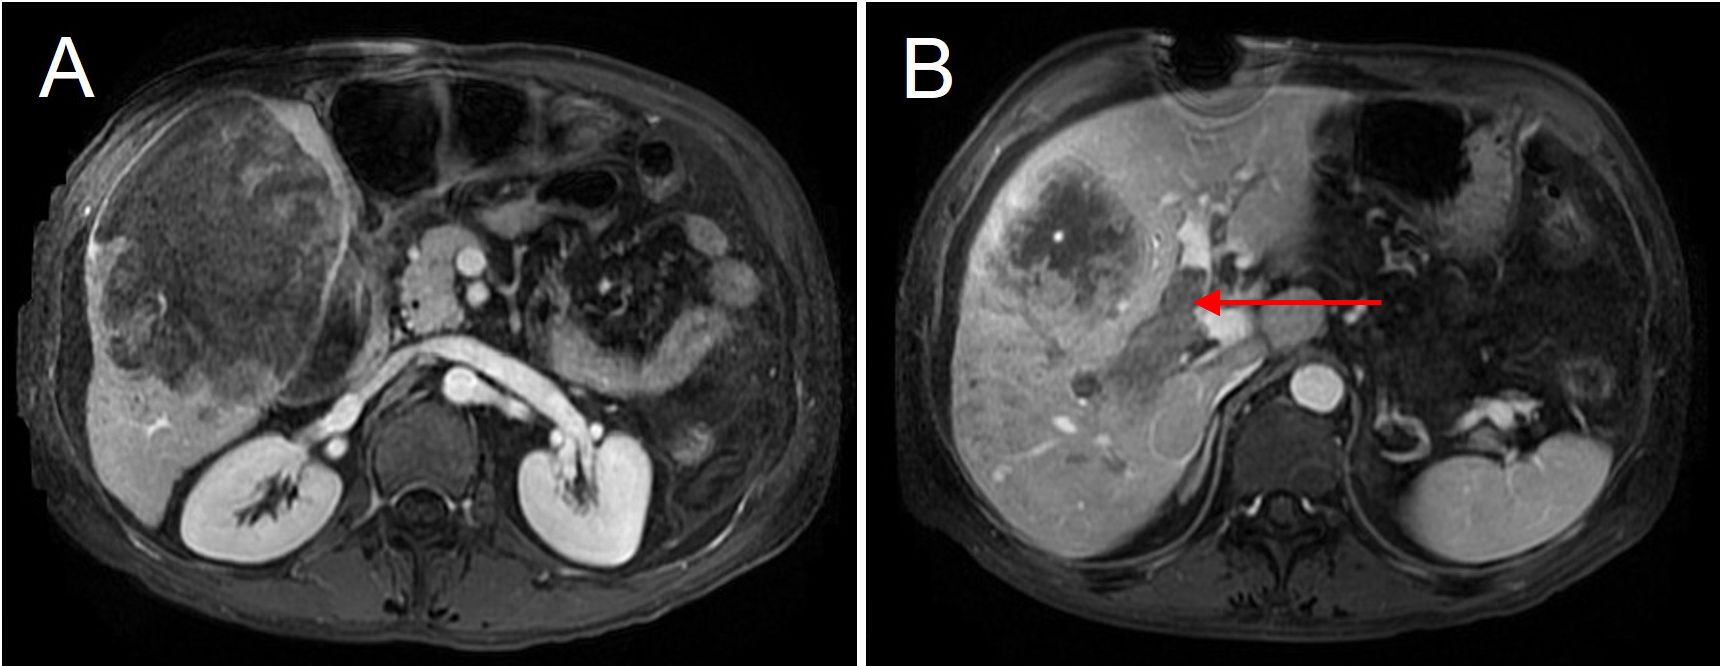

A 55-year-old male with a history of chronic hepatitis B infection and alcohol-related cirrhosis was admitted to the hospital due to acute abdominal pain and hemodynamic instability. In addition, twelve years earlier, the patient underwent surgical repair for a perforated gastric ulcer and recovered well after the operation. Upon this admission, Contrast-enhanced MRI revealed a ruptured hepatocellular carcinoma (HCC) in the right hepatic lobe, measuring approximately 150 × 110 × 100mm, accompanied by portal vein tumor thrombus (PVTT, Cheng’s type II) (Figure 1).

Figure 1

Preoperative MRI showing a giant hepatocellular carcinoma in the right hepatic lobe. (A) The tumor measures approximately 15 cm × 10 cm in size. (B) The right portal vein is completely filled with tumor thrombus (red arrow), indicating portal vein invasion by the tumor.